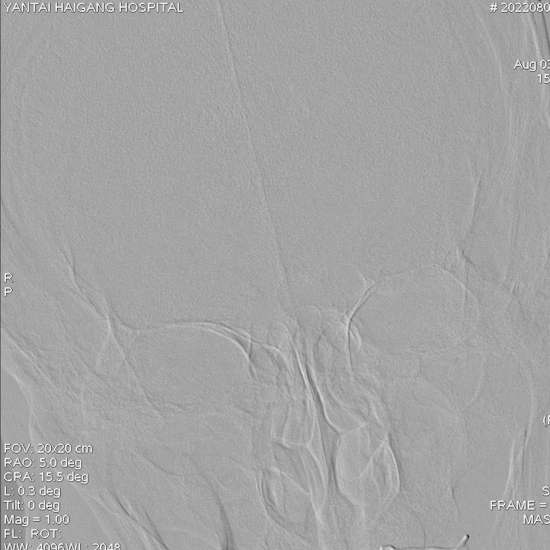

入院影像资料

内科治疗后仍有新发梗死(2022.8.8):

导丝怎么扩【载药时代 球扩天下】NOVA DES®颅内药物洗脱支架在椎动脉颅内段重度狭窄的应用二例_https://www.jmylbn.com_新闻资讯_第8张

导丝怎么扩【载药时代 球扩天下】NOVA DES®颅内药物洗脱支架在椎动脉颅内段重度狭窄的应用二例_https://www.jmylbn.com_新闻资讯_第9张

重要影像结论:桥脑新发亚急性梗死灶,右侧椎动脉重度狭窄。